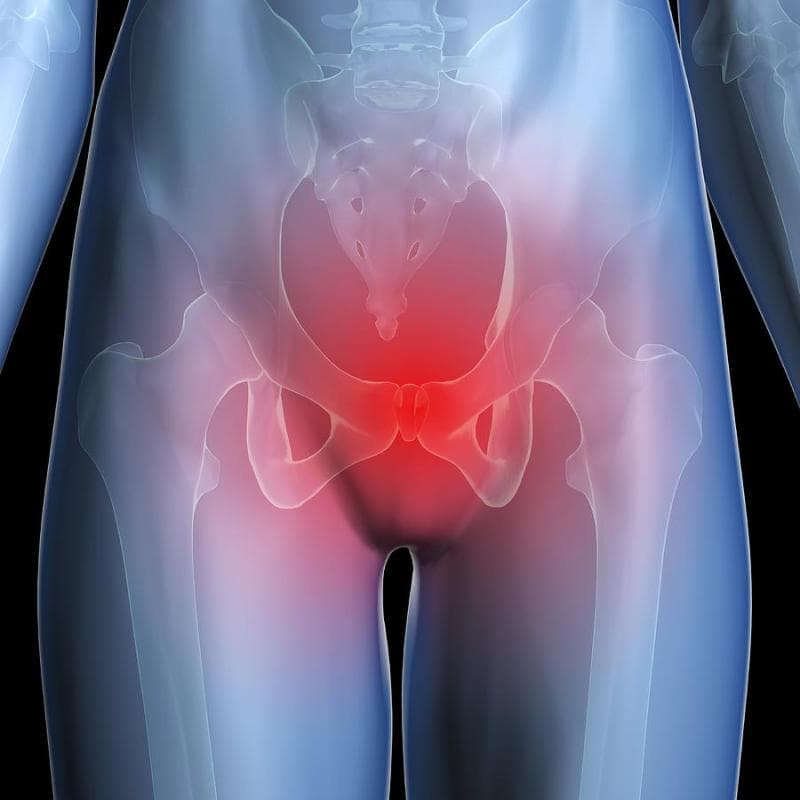

Боль в малом тазу у женщин: Причины и подходы к лечению